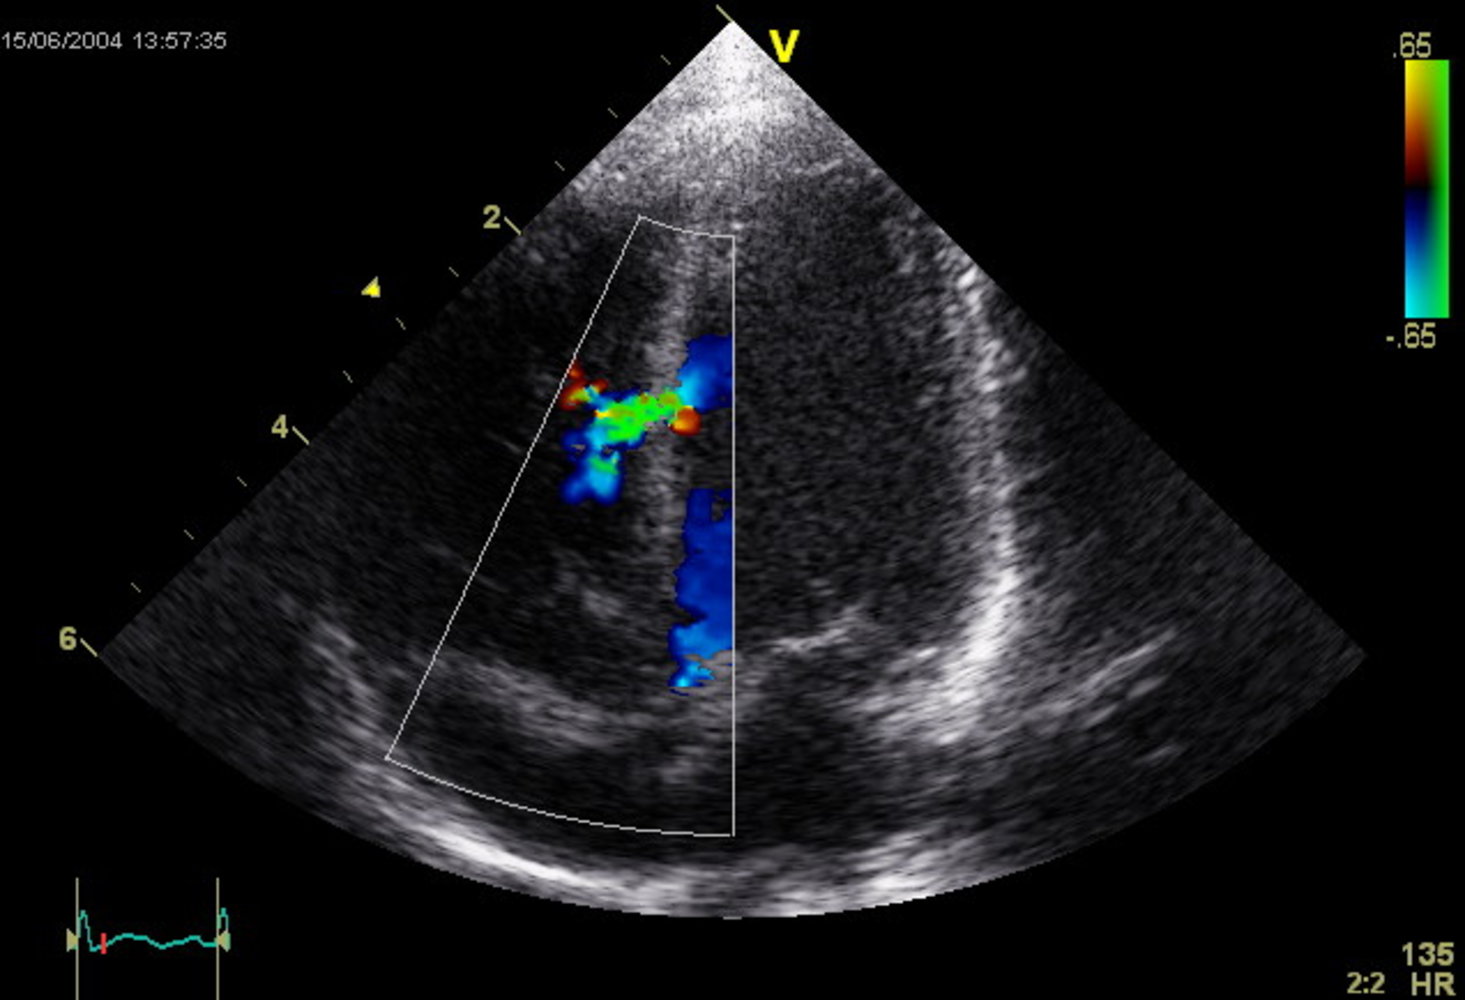

Echocardiography: (confirmatory test): TTE is preferred over TEE. [28]

- To assess defect size, shunt volume, Qp:Qs ratio, and associated conditions, e.g., ↑ pulmonary artery pressure, outflow obstructions

- Doppler echocardiography is especially helpful for visualizing small VSDs.

Echocardiography (confirmatory test) :

-

TTE with Doppler

- Confirms interatrial communication

- Best visualized in the apical four-chamber and subcostal views